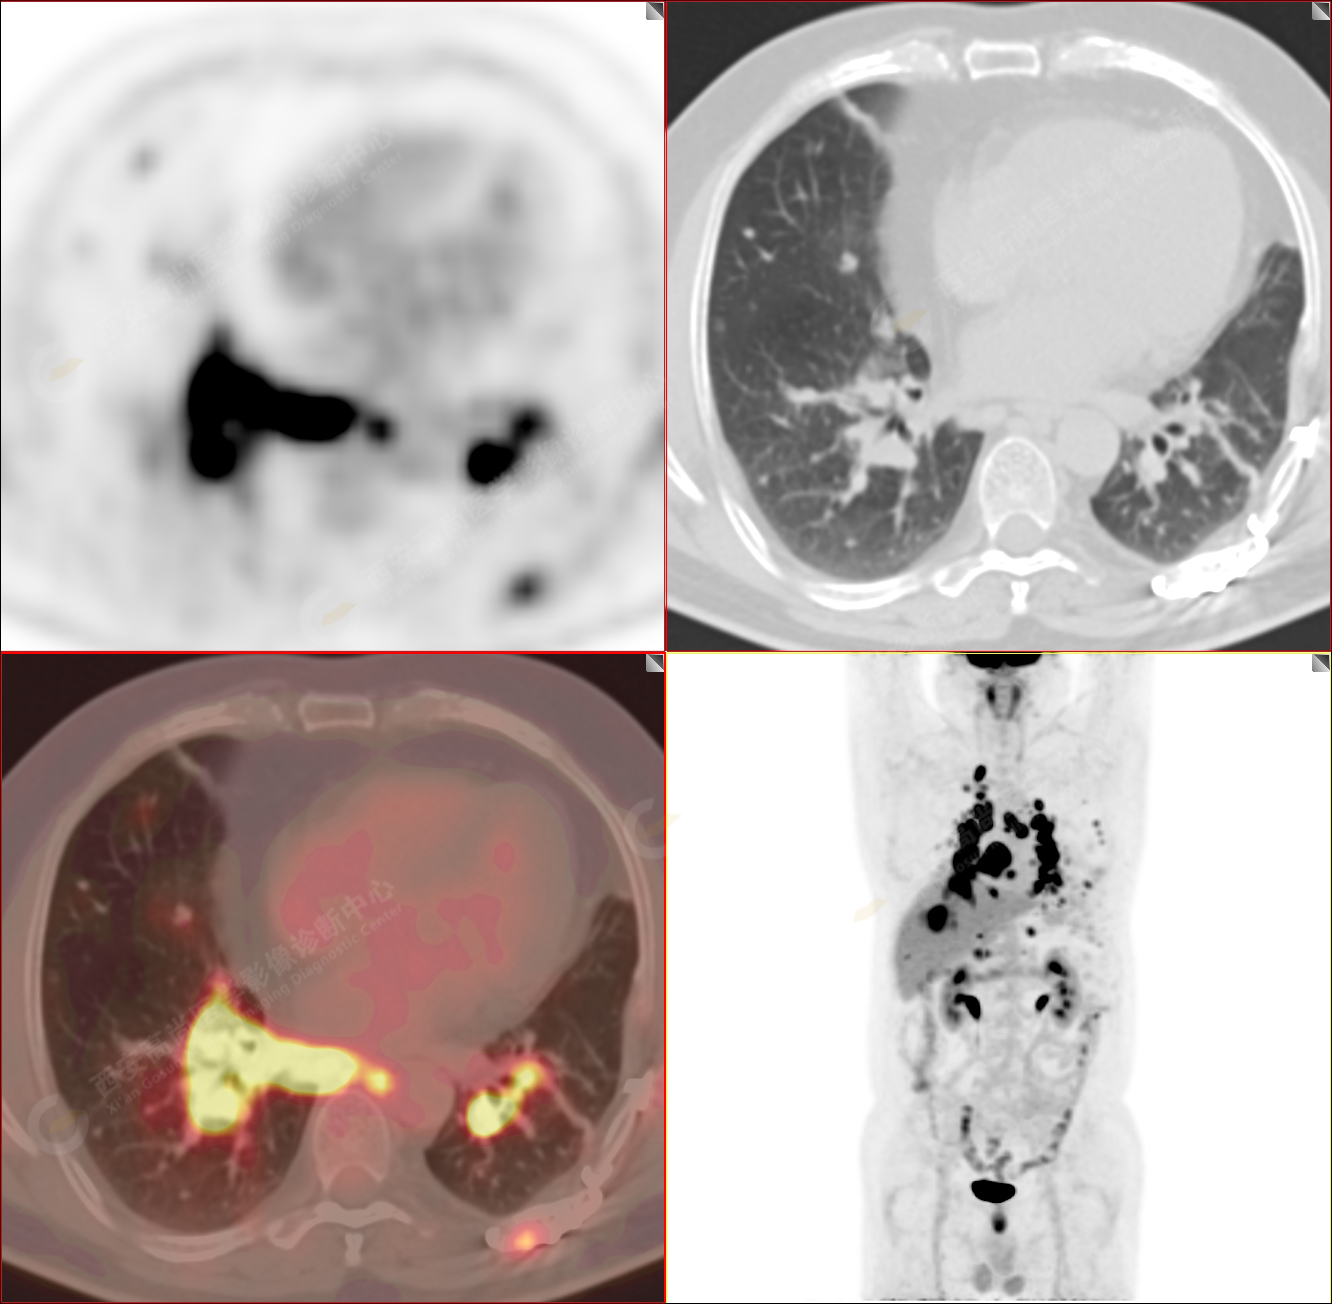

PET/CT-MR診斷結(jié)節(jié)病雙肺及全身多發(fā)淋巴結(jié)廣泛累及1例【西安高尚病例】

男性,53歲,頭暈半月入院,CT發(fā)現(xiàn)肺內(nèi)腫塊,雙肺多發(fā)大小不等實(shí)性及粟粒樣結(jié)節(jié),雙肺門(mén)及縱隔多發(fā)腫大淋巴結(jié)。病程中無(wú)發(fā)熱、胸悶氣及胸部不適。既往:左側(cè)肋骨外傷史。

PET/CT圖像